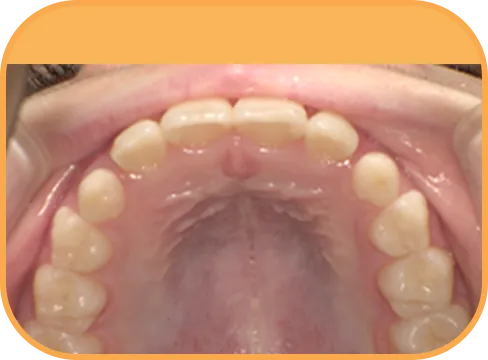

• Before

• 正 面

治療前正面からの歯の様子

• 上 顎

治療前上顎からの歯の様子

• 下 顎

治療前下顎からの歯の様子

• 右 側

治療前右側からの歯の様子

• 左 側

治療前左側からの歯の様子

主 訴

前歯がでている、噛み合わせが深い

治療内容

インビザライン・ファースト

治療期間

10か月

治療費(税別)

450,000円+診断料30,000円

リスク・副作用

• 親知らずの影響や加齢などによって、凸凹が生じる可能性があります。

• 治療の初期段階では痛みや不快感が生じやすくなりますが、1週間前後で慣れます。

• 顎の成長発育によって、噛み合わせや歯並びが変化する可能性があります。

• 状況により当初予定した治療計画を変更する可能性があります。